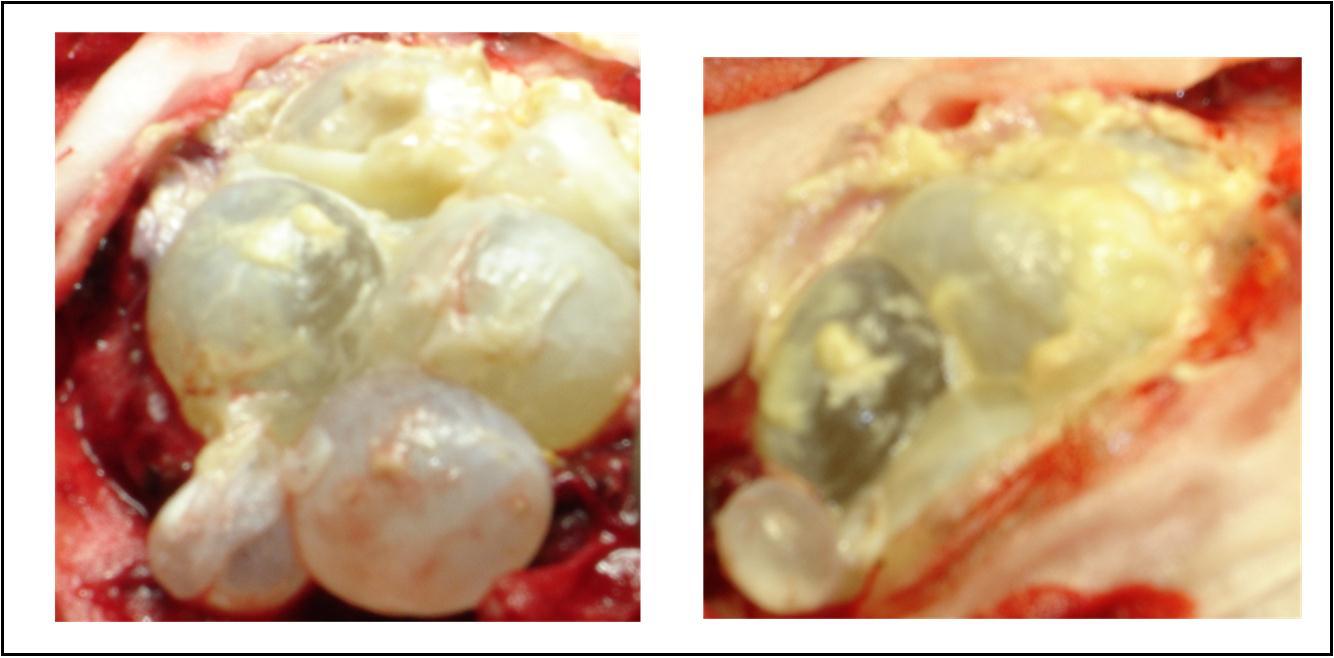

A 27 years-old male patient was admitted with 1 month history of headache, fever, short term memory lack, aphasia, right hemiparesis and seizures. He had liver hydatid cysts excised 8 years before and was treated with adjuvant medication (albendazole). The neurological examination revealed right central third cranial nerve palsy and hemi paresis, with Babinski sign positive, aphasia and papilledema on ocular fundus. The Glasgow Coma Scale was evaluated to 10/15 (E:3; V:1; M:6). A brain CT scan showed a large left temporoparietal intracerebral multiple and calcified hydatid cysts, important mass effect with midline shift about 7 mm following by an obstructive hydrocephalus (Figure 1). Other cysts were found in thalamic region (Figure 2). The Thoraco-abdominal CT scan showed multiple intra peritoneal hydatid cysts (Figure 3). A left temporo parietal craniotomy was performed in emergency. After corticectomy, using Arana-Iniguez technique, the appearance of the capsule suggested infected hydatid cysts with a purulent material which was aspirated. Numerous hydatid cysts were lifted away and several daughter vesicles were carefully removed without rupture (Figure 4). Macroscopically, the abscess wall appeared to be thick, calcified and tightly attached to lateral ventricular, so it could not be removed. The deep cyst overlying the third ventricle was left.in place. Microscopic examination demonstrated live scoleces, protoscoleces and multiple hooks. These findings are consistent with hydatid cyst (granulosis ecchinococcus) (Figure 5). Bacteriology examination found several white blood cells in the pus (neutrophilia) and infection by streptococcus pneumonia. This was consistent with infection. After surgery, the patient had medication (albendazole, specific antibiotherapy and phenobarbital). The inflammation assessment in the blood showed leukocytosis, a high C-reactive protein rate and increased erythrocyte sedimentation rate. Post operative CT scan was performed and showed the residual calcified capsule and decreased ventricular size (Figure 6). Clinical improvement was achieved after treatment. One month after the initial diagnosis, CT scan of the brain showed no recurrence and a physical examination revealed a neurologically intact, fully functional patient and eyes fundus normal. He was discharged and went to abdominal surgery two months later with complete intra abdominal cysts removal. Albendazole treatment was continuing for six months and radiological exploration was performed by brain MRI with spectroscopy at three and six month later. This showed that infection had resolved and the deep cyst overlying the third ventricle is less spherical (Figure 7, Figure 8). Four years later, the outcome was good.

Figure 4.per operative view showing multiple hydatid cysts with purulent material